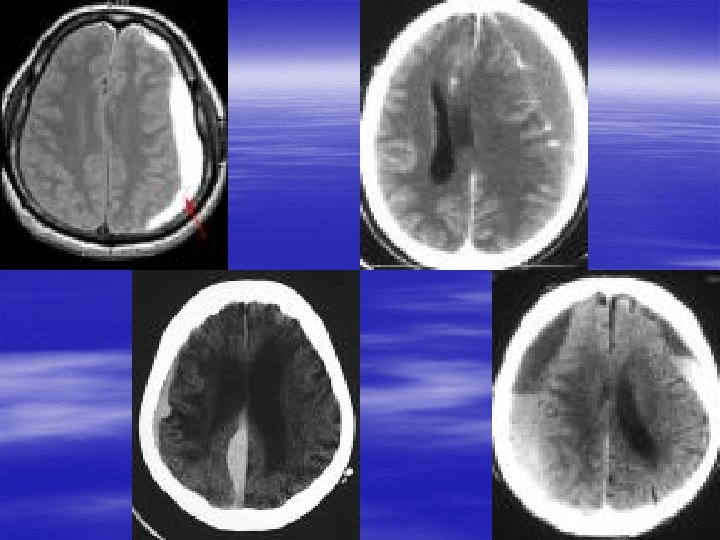

Specific Head Injuries § Traumatic Subarachnoid Hemorrhage – Most common CT finding in moderate to severe TBI – If isolated head injury, may present with headache, photophobia and meningismus – Early t. SAH development triples mortality – Size of bleed and outcome – Timing of CT – Nimodipine reduces death and disability by 55%